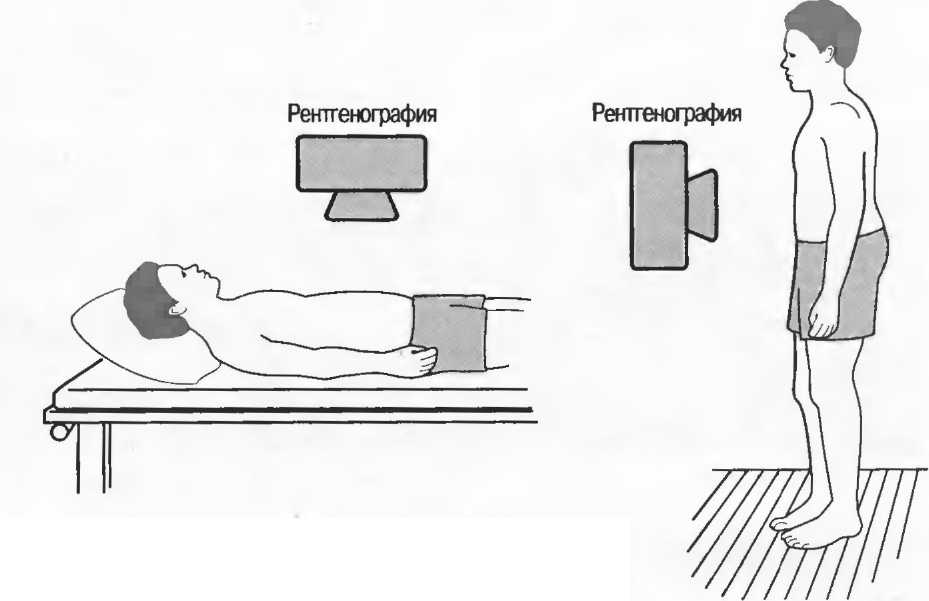

Получение диагностического изображения считается важным вспомогательным методом к клиническому исследованию при оказании медицинской помощи больным, страдающим многими распространенными заболеваниями. В основном диагностическое изображение получается с помощью рентгенографии и ультразвукового сканирования. В рамках цели Всемирной организации здравоохранения достижения здоровья для всех много таких исследований будет проводиться на первом уровне специализированной помощи, куда будут направлены пациенты либо с уровня первичной медико-санитарной помощи, либо те, кто нуждается в неотложной помощи. Во многих странах нет достаточного числа рентгенологов или специалистов по эхографии для того, чтобы обеспечить квалифицированное выполнение исследований и их интерпретацию, и получение диагностического изображения может назначаться, интерпретироваться и проводиться медицинскими работниками, имеющими недостаточные специальную подготовку и опыт или не имеющими их вообще.

Это руководство является одним из нескольких, опубликованных Всемирной организацией здравоохранения с целью дать рекомендации по использованию диагностического изображения неспециалистами1. Проведение ультразвуковых исследований быстро распространяется во всем мире; особо важное значение такие исследования имеют в акушерстве, они также дают полезную информацию в отношении брюшной полости и мягких тканей. В связи с отсутствием ионизирующей радиации ультразвуковое исследование должно быть предпочтительным методом, обеспечивающим изображение, в случаях получения полезной клинической информации.

Для маленькой больницы или клиники рентгенография (такая, как обеспечивается Радиологической системой ВОЗ) должна оставаться на первом месте среди методов получения диагностического изображения, несмотря на то что ультразвуковое исследование может быть заманчивым, так как оборудование является менее дорогостоягцим и явно менее сложным. Тем не менее с помощью ультразвука нельзя получить изображения легких, переломов и большинства других патологий скелета, поэтому ограничения данного метода следует принимать во внимание.